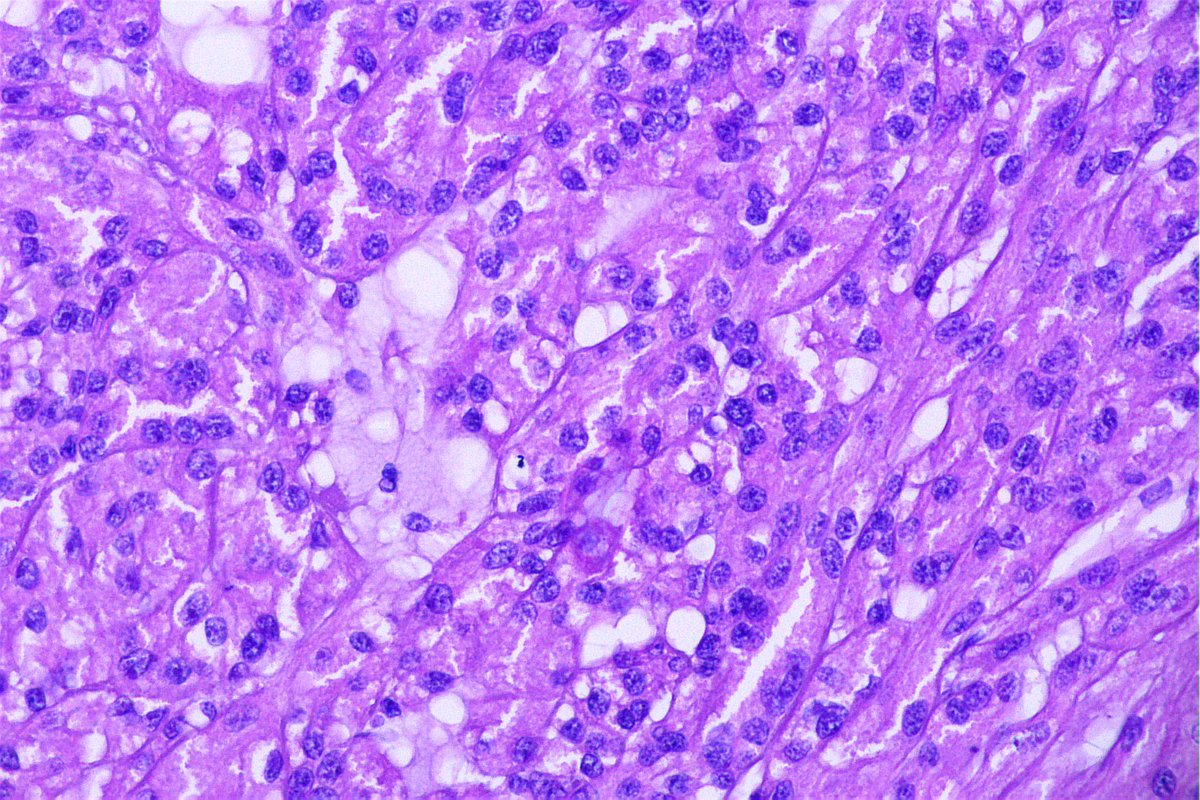

@GeronimoJrLapac

Ger么nimo Jr.

2 months

F, 47yo. The clinical information is: subepithelial lesion in the ileocecal valve. #gipath